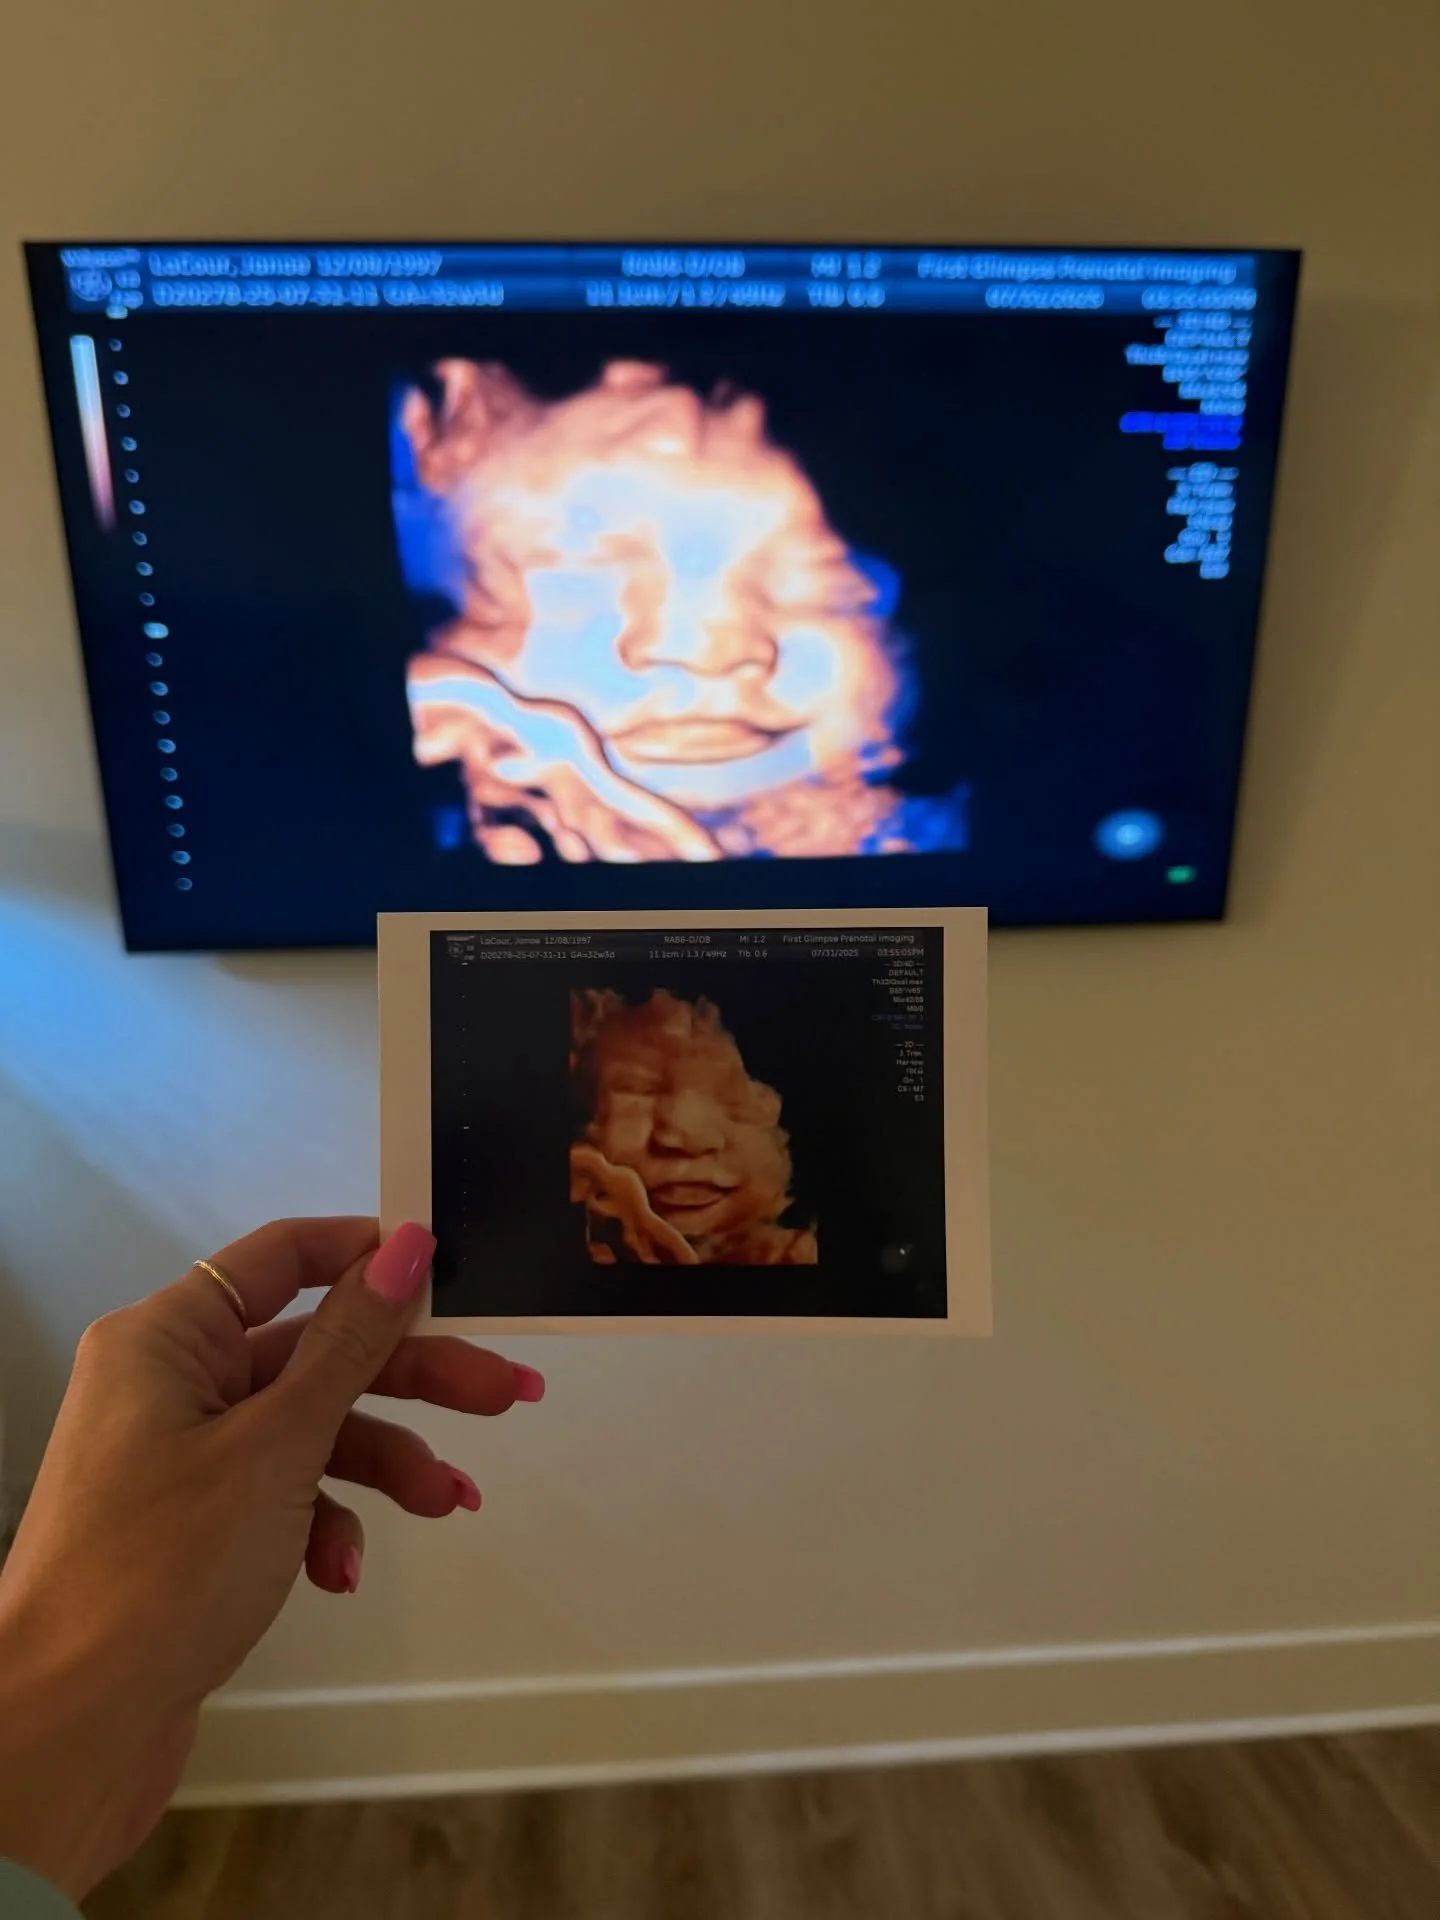

Ultrasound Packages

A WARM & INVITING ENVIRONMENT TO CREATE MEMORIES

that will last a lifetime.